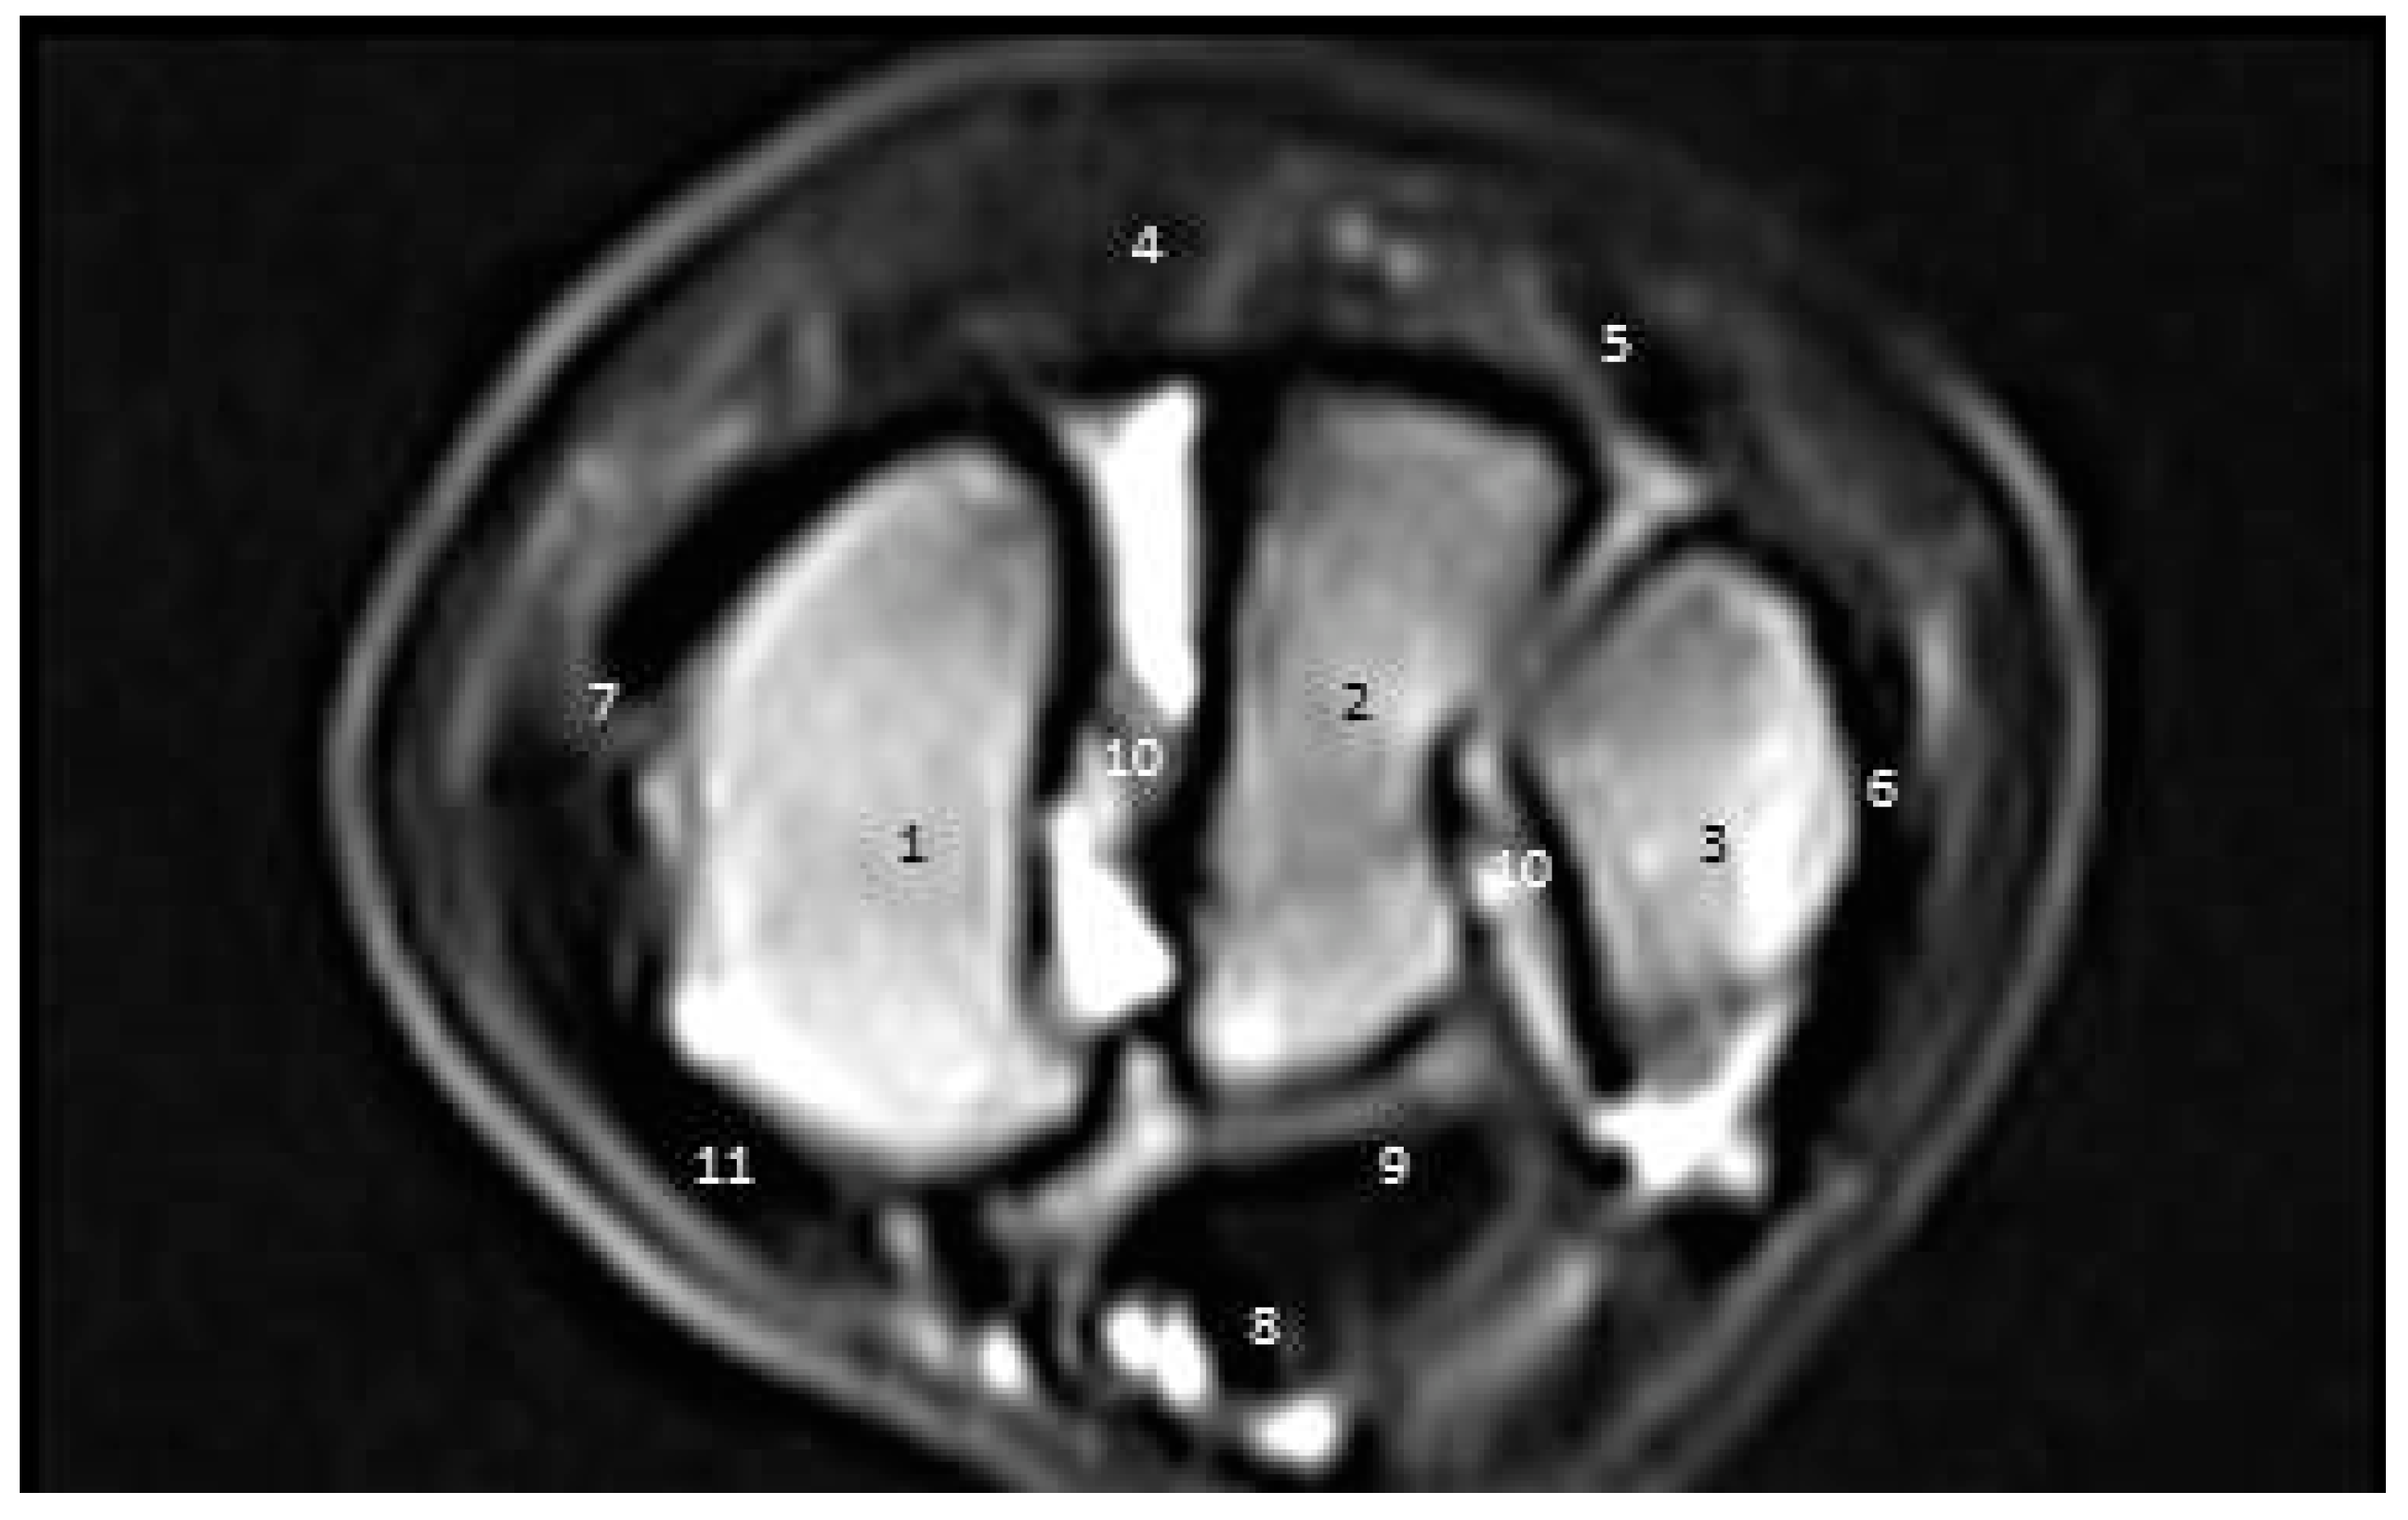

3.3.3. Third Zone